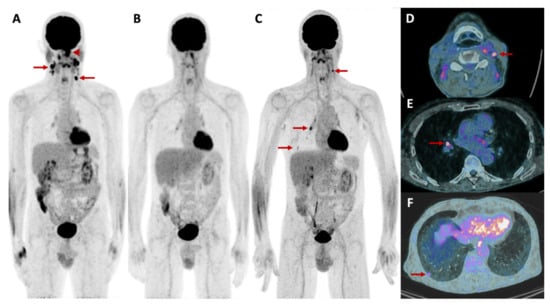

2.5.3. Metabolic and Receptor-Specific Imaging

2.5.4. Combined Modalities